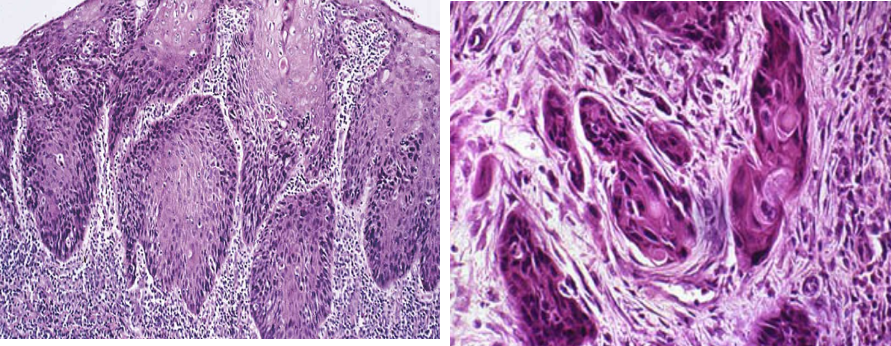

镜下,组织学类型分为:

①鳞状细胞癌:最常见,达90%,依分化程度分高、中、低三级;

②腺癌:不多见,与Barrett食管相关,亦依分化程度不同分三级;③未分化癌,较少见,恶性程度高。